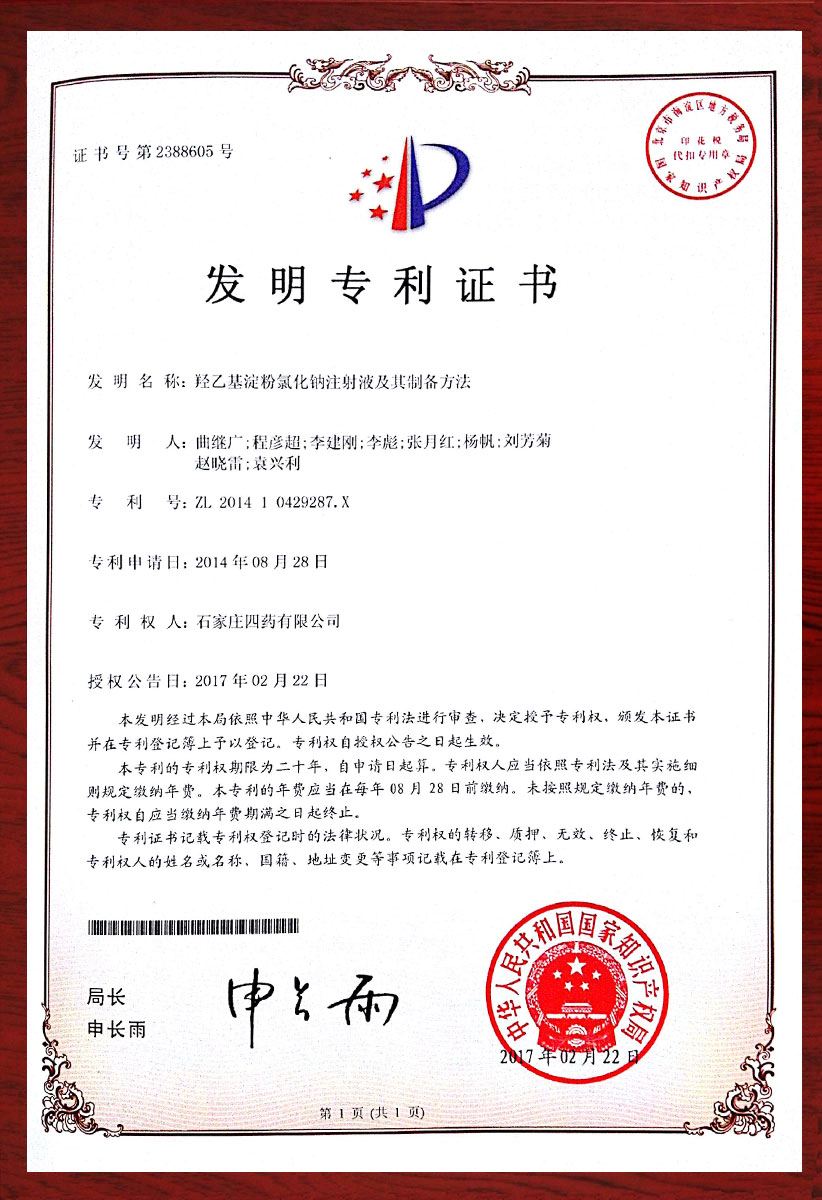

专利证书